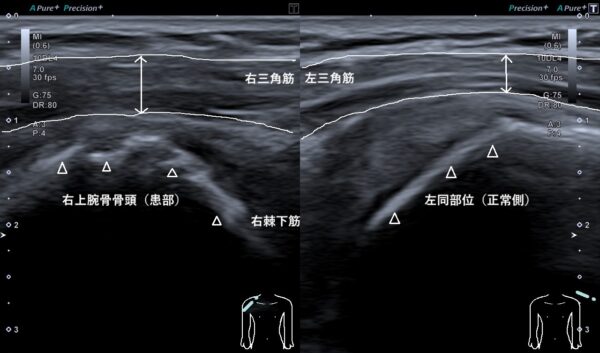

それらの所見から、超音波(エコー)画像検査を行うと右三角筋の中の白い線(筋肉を包む膜)が損傷(消失)して腫れていました(画像、矢印の長さの比較)。

さらに、右上腕骨骨頭が左と比較して骨の表面が不整(デコボコしている)で変形性肩関節症になっていました(画像、矢頭上の白い線)。